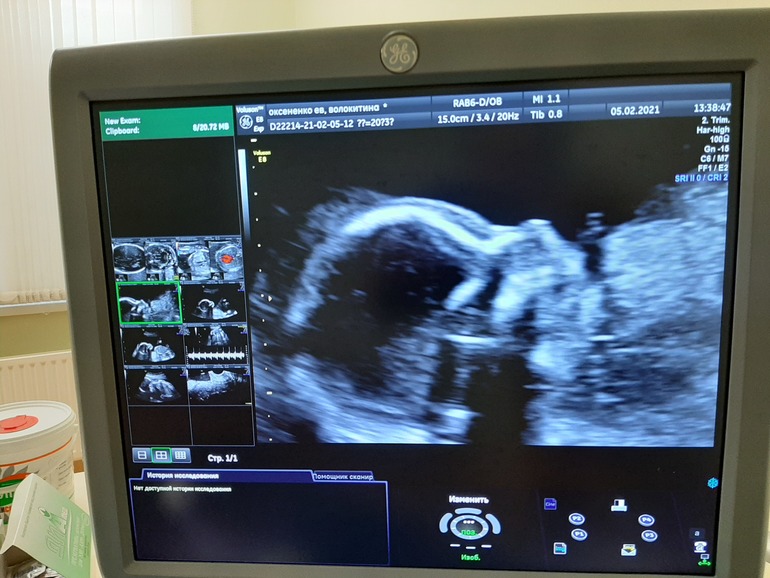

Ах ну и фото, с монитора правда, нашей Евишны-королевишны, оооох так и приалепится имя 🤷♀️....

Говорю, на меня похожа, врач посмотрела говорит, нет нос не ваш 🤣🤣🤣. Чтобы она понимала 🙈🤣

Ну да ладно. Пришла на УЗИ, врач смотрела в основном молча, напряглась не много, но не много терпения, как все замеры сделала, только потом задала ей несколько вопросов, по УЗИ все хорошо сердечко 151 чсс, спросила кто там)), она сказала мне кажется девочка, таааак как это кажется 🤣, переспрашиваю: "Точно?" Она улыбается и между делом: "Точно!". А мне снова не верится)))) Но других вариантов нет, я с первого дня чувствую дочку, боюсь поверить, но там точно не парень😂.

336 гр, нашего счастья😍😍😍!!